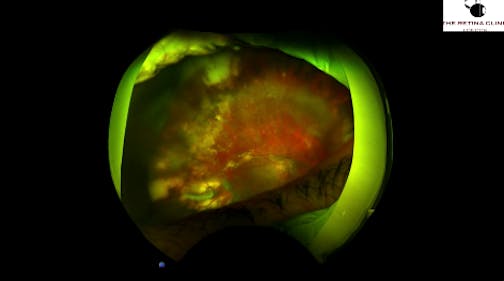

Retinal Detachment

Kazuaki Kadonosono, MD